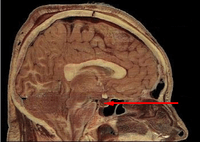

- HPA axis, explains the connections of the hypothalamus, pituitary and adrenal glands